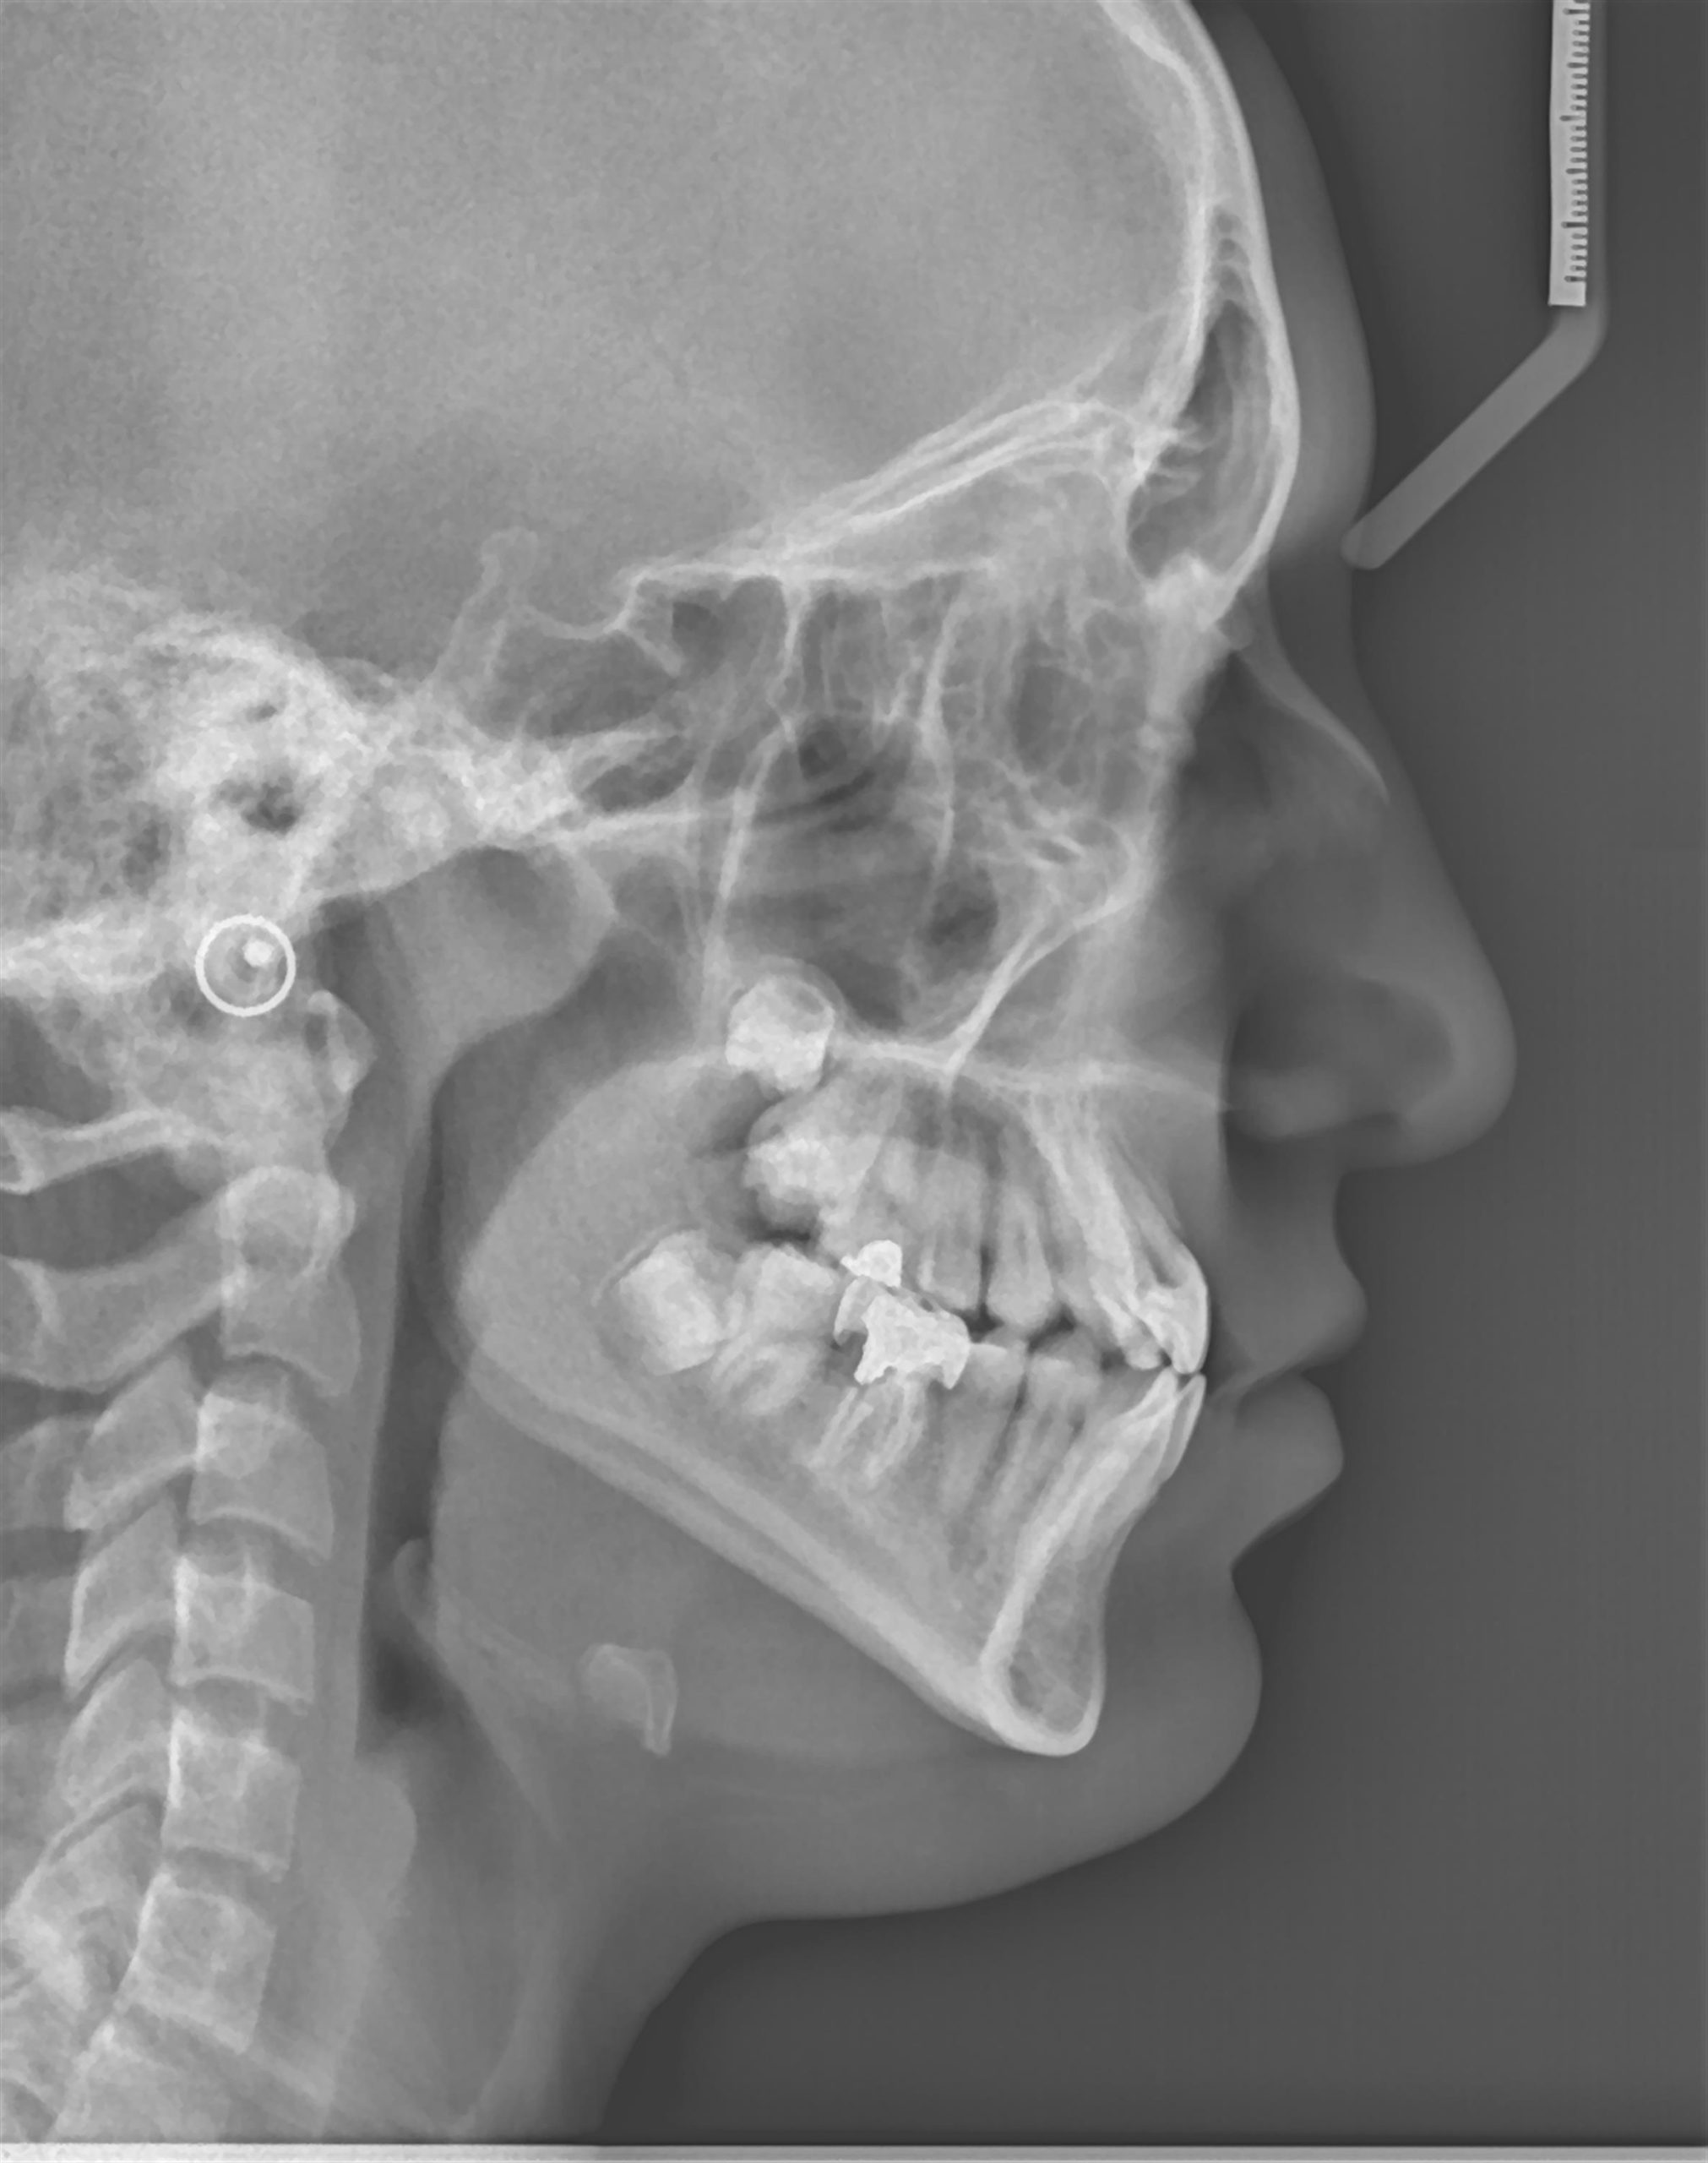

- رادیوگرافی لترال سفالومتری وسایر رادیوگرافیهای جمجمه